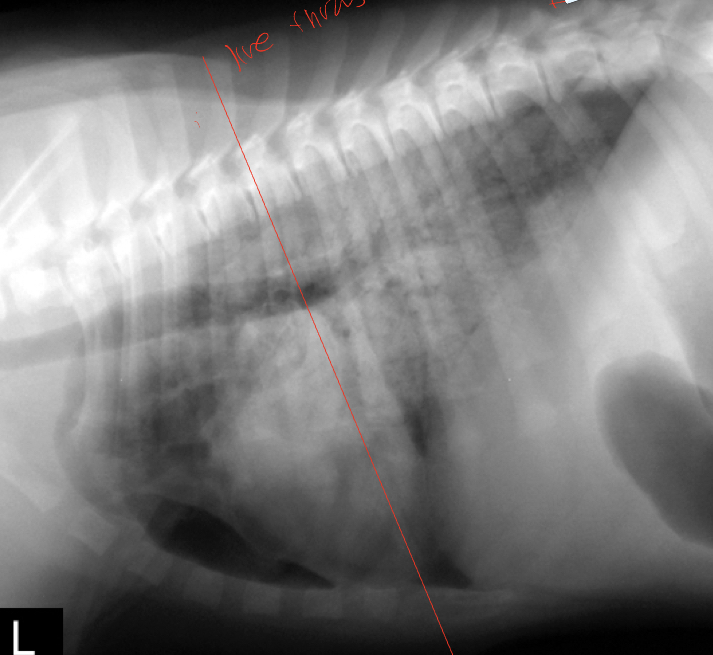

14

Q

what lung pattern and ddx

A

cranioventral

Ddx: pneumonia, hemorrhage, neoplasia

15

Caudodorsal

Ddx: cardiogenic or non-cardiogenic pulmonary edema